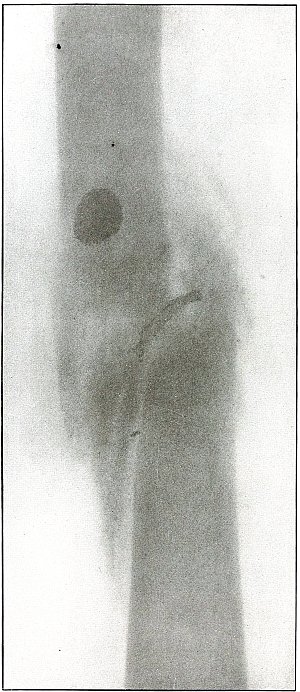

| 59. |

Gunshot wound, knee |

128 |

| 60. |

| 128.[Pg 6] |

Gunshot wound, knee |

266 |

| 129. |

Gunshot wound, knee |

268 |

| 130. |

Gunshot wound, knee |

270 |

| 131. |

Gunshot wound, knee |

272 |

| 132. |

Gunshot wound, knee |

274 |

| 133. |

Gunshot wound, knee |

276 |

| 134. |

Gunshot wound, knee |

278 |